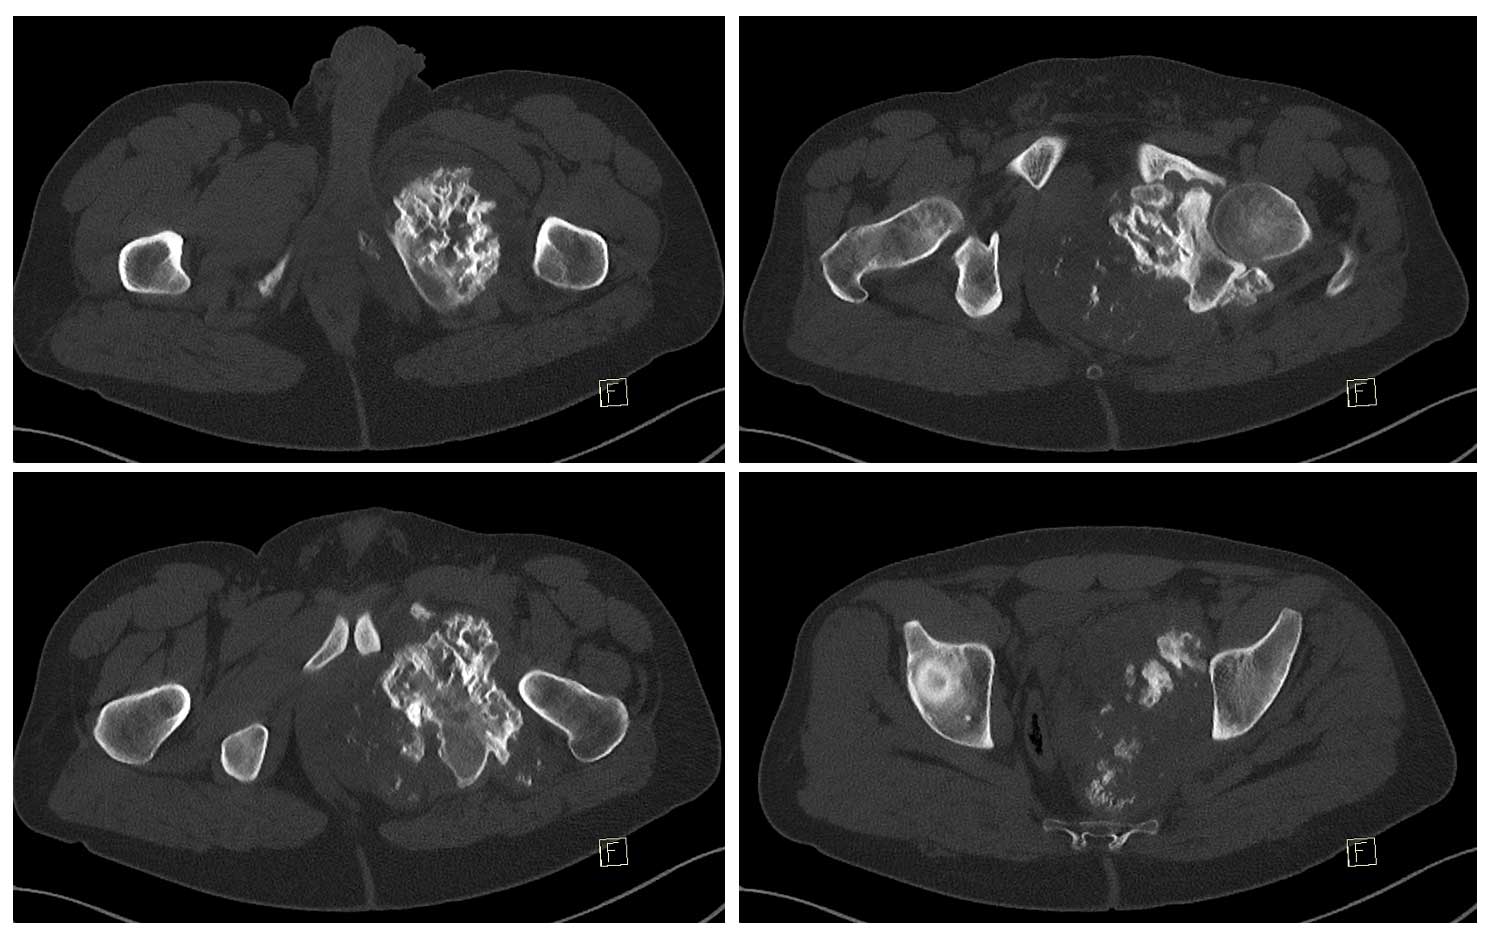

Ameliyat Öncesi: Röntgen ve 3BT’de sol asetabulum ve pubik kol kaynaklı obturator foromani ve hemipelvisi dolduran düzensiz sınırlı sklerotik tümör dokusu görülmekte.

Ameliyat Öncesi: Tomografide kemik yüzeyde harabiyete neden olan kalsifikasyon içeren düzensiz sınırlı kitle görüntüsü görülmekte.